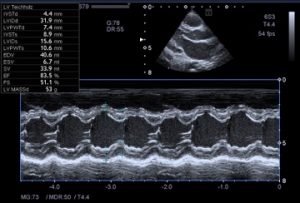

Modo-M: el haz se produce a lo largo de una línea, apareciendo los ecos como puntos de diferente intensidad, en el eje vertical se representan los puntos y el tiempo en el horizontal, su uso más frecuente para la función del ventrículo izquierdo.

También se utiliza para el estudio de la función del ventrículo derecho mediante el desplazamiento del anillo tricuspideo (denominado tricuspid annulus plane systolic excursion o TAPSE ), que mide en milímetros el desplazamiento del anillo, a mayor desplazamiento mejor contracción longitudinal del ventrículo derecho (en adultos el valor es más de 16mm en niños depende de la edad)